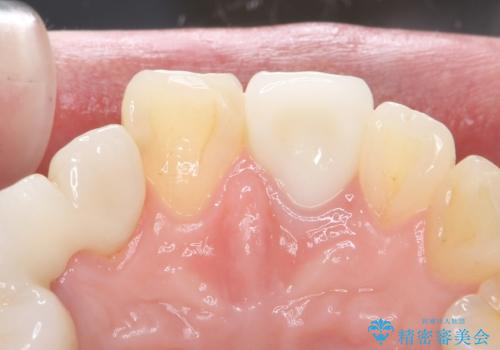

歯ぐきの状態も良く、適合の良い被せ物を入れることができました。

審美性もかなり改善され、大変喜んでいただけました。